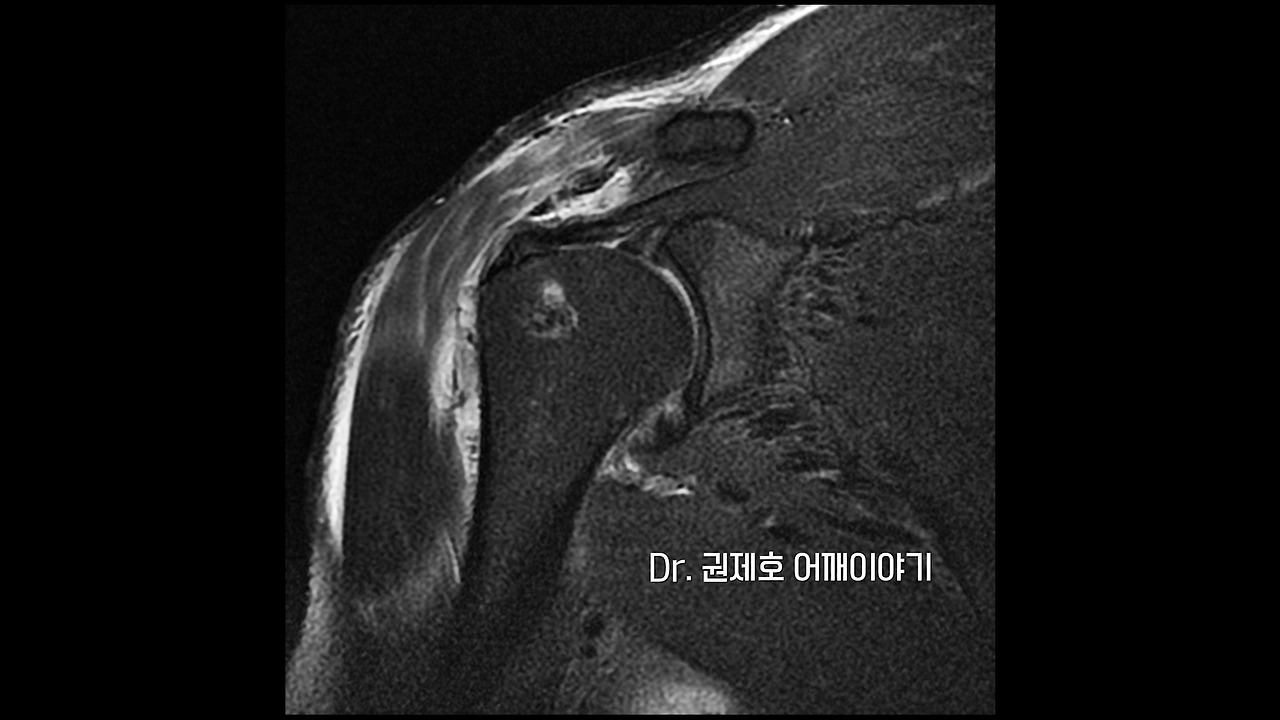

MRI를 보는 이유는 모든 것을 보기 위함입니다. 위에서 화살표 방향을 보면 알겠지만 검은색의 끈 모양이 가는 중에 끝에서 흰색의 빈 공간이 생기는 것을 알 수 있습니다. 검은색으로 보이는 것이 어깨 인대이고, 끝에서 흰색 빈 공간이 생기는 것이 어깨 인대 파열을 의미하는 소견입니다. 즉 힘줄이 뼈에서 뜯긴 상황 혹은 끊어진 상황입니다.